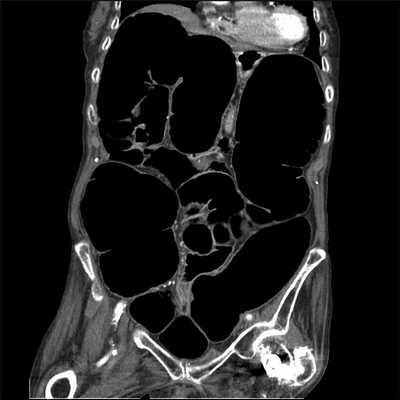

- Рентген брюшной полости часто показывает массивное расширение толстой кишки (мегаколон) с диаметром слепой кишки 10-14 см.

- КТ часто проводится для исключения механической обструкции.